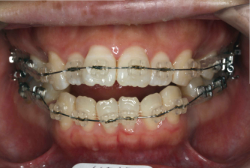

「ものがうまく噛めない」という主訴で来院したケースです。診断の結果、「骨格性反対咬合に伴う咬合不良+軽度叢生」と判明しました。原因としては特に下顎の左側が過成長したため、骨格性反対咬合になり、特に左側での噛み合わせが非常に悪くなっていると診断しました。初診時の写真を見ると、上下の正中線の大きなズレ、左側の噛み合わせの不良がはっきり分かります(黄色の矢印と緑の矢印は一致しているのが正しい状態です)。

そもそも、このような状態となっているのは骨の大きさに問題があるため生じていますので、場合によっては、「外科矯正」によって下顎の骨を外科的に縮めることで修正します。患者様が外科矯正をご希望されない場合は、従来ですと上下左右の小臼歯抜歯を行い矯正するのが普通です。

今回の患者様の場合は、「外科」も「小臼歯抜歯」も拒否されましたので、歯科矯正用アンカースクリュー(以下 アンカースクリュー)を用いて、下顎の歯列全体を後方に下げるという方法を取りました。

治療中の写真で、アンカースクリューより歯を後ろへ牽引しているのがお分かりいただけるかと思います。牽引を1年ほど続け、途中補助的に上下にゴムをかける(これを顎間ゴムと言います)手法なども追加し、全体で21ヶ月で治療を終えることが出来ました。

結局歯の本数を減らすことなく、すべてご自分の歯を残して、正しい配列と噛み合わせにすることができました。凸凹があまりひどくないため、簡単そうに見えると思いますが、このケースの初診の状態を見ると、熟練の矯正歯科医でも悩みのつきないケースです。まして、外科も出来ない、抜歯もイヤ、と言うことになると、従来の方法では治療不可能と考えられるのですが、アンカースクリューを使うことで最近は不可能が可能となってきました。